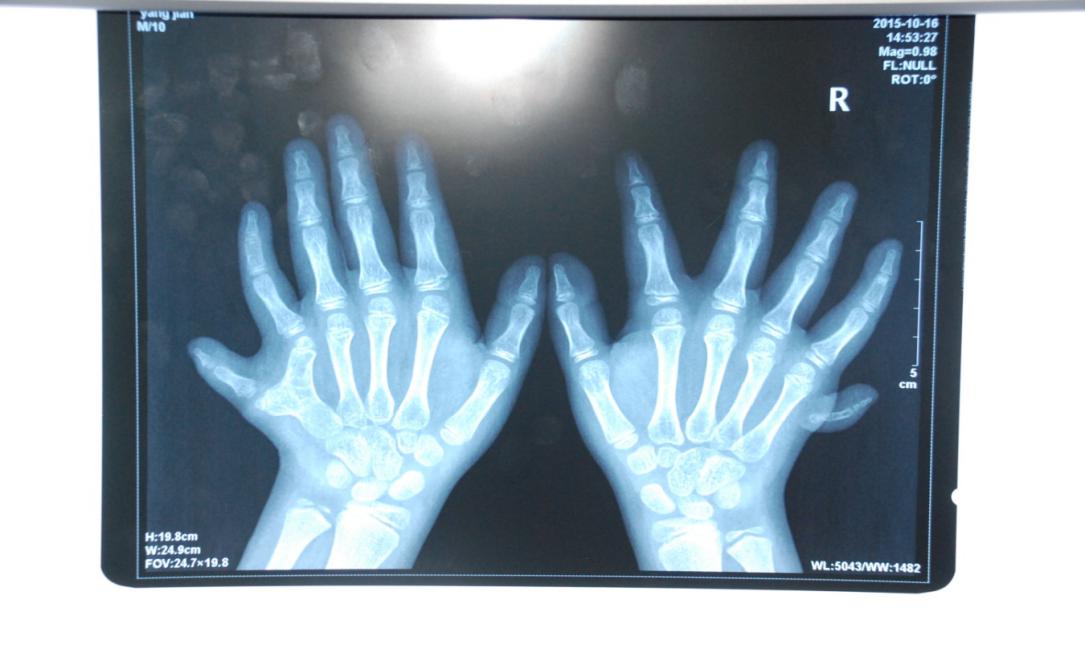

廈門眼科中心小兒眼科修陽暉博士在日常的診療過程中就接診了不少這樣的的特殊家庭,讓其尤為印象深刻的就是一年前接診的BBS綜合征患者。當(dāng)時來院就診的是一對親兄弟,之前已在多家醫(yī)院做過檢查,因其均有較大散光和斜視,肉眼下眼底檢查未見異常,故外院均診斷為弱視,這也符合眼科門診常規(guī)的診斷邏輯與思維。但由于兄弟倆均有智力發(fā)育遲緩、特殊面容及四肢均有六指和六趾的特異體征引起了修陽暉博士的警覺:會不會是一種特殊遺傳性疾病或綜合征?后續(xù)的檢查結(jié)果進一步證實了修陽暉博士的懷疑---患兒均有夜盲,ERG、VEP及OCT檢查顯示雙眼的視網(wǎng)膜神經(jīng)上皮層結(jié)構(gòu)及功能均明顯異常。由于之前未遇到此種病例,修陽暉博士在診斷一欄寫下視網(wǎng)膜色素變性并打上了個問號,同時留下了病人的聯(lián)系方式。

BBS綜合征(Bardet-Biedl綜合征)是一種主要累及纖毛結(jié)構(gòu)與功能的罕見常染色體隱性遺傳性疾病。纖毛分布于哺乳動物體內(nèi)的大多數(shù)細胞,它是一種廣泛存在于各種細胞表面的細胞器,體型微小但結(jié)構(gòu)復(fù)雜、作用強大,能感知細胞外機械和化學(xué)信號變化并協(xié)助其轉(zhuǎn)導(dǎo)到細胞內(nèi)部從而引起細胞應(yīng)答。高等動物的視覺、觸覺、嗅覺、聽覺的傳遞都依賴于體內(nèi)外正常的纖毛結(jié)構(gòu)和功能。因此BBS綜合征常累及全身多個系統(tǒng)和器官,在臨床上主要表現(xiàn)為:視網(wǎng)膜色素變性、智力發(fā)育異常、向心性肥胖、多指(趾)、性腺發(fā)育異常、腎臟異常。除此之外還有許多諸如:語言發(fā)育障礙、聽力異常、嗅覺異常、斜視、白內(nèi)障、散光、牙齒發(fā)育異常、短指(趾)、并指(趾)、肝纖維化、糖尿病、高血壓等表現(xiàn)。